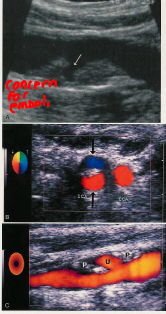

what types of ulcerative plaque are there?

what is it a concern for?

Ulceration:

heterogeneous

sharp, irregular borders

≥ 2mm defect

Intraplaque hemorrhage (IPH) from vaso vasorum:

sonolucent region

eggshell pattern

embolism